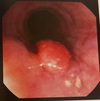

9

Papiloma